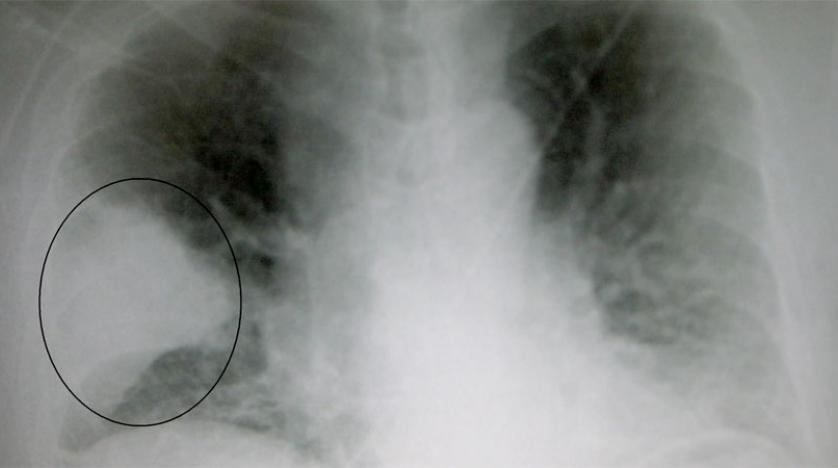

أعلنت الصين السبت وفاة رجل عن 61 عاماً أصبح أول ضحية لمرض تنفسي يعتقد أنه ناجم عن فيروس من سلالة متلازمة التنفس الالتهابي الحاد (سارس) التي أودت بمئات الأشخاص قبل أكثر من عقد. وتم تسجيل 41 حالة حتى الآن لأشخاص ظهرت عليهم عوارض شبيهة بالالتهاب الرئوي، باعتبارها إصابات بالفيروس الجديد في مدينة ووهان وسط الصين توفي أحدهم الخميس، وفق ما أفادت مفوضية الصحة في ووهان على موقعها الإلكتروني. ولايزال سبعة أشخاص في حالة الخطر، انتهى علاج اثنين منهم، فيما الآخرون في حالة مستقرة، وفق مفوضية الصحة. وأثارت تلك الإصابات حالة من الذعر، إذ خيّم شبح فيروس سارس الذي أودى بين 2002 و2003 بحياة 349 شخصاً في البر الصيني، و299 في هونغ كونغ التي تضرر اقتصادها بشكل كبير بسبب تأثير الفيروس المدمر على السياحة.

وأعلنت مفوضية الصحة في ووهان أن الرجل المتوفى كان قد اشترى سلعاً من سوق سمك في المدينة، أكدت السلطات أنه مركز تفشي المرض. وتم إغلاق السوق في الأول من يناير، والرجل الذي كان يعاني مشكلات صحية، منها مرض مزمن في الكبد، توفي في المستشفى الخميس من «فشل رئوي والتهاب رئوي حادي» وفق المفوضية. ولم يتم تسجيل حالات إصابة أخرى منذ الثالث من يناير ولا أي «دليل واضح على انتقال (الفيروس) بين البشر». وقالت منظمة الصحة العالمية الخميس إنها لا توصي بأي تدابير محددة للمسافرين أو أي قيود على التجارة مع الصين. كما عبرت عن الثقة بقدرة السلطات الصينية على احتواء الفيروس. ودخلت الصين فترة السفر المرتبط بعطلة السنة القمرية الجديد، ما يثير المخاوف من تسبب حركة التنقل الكبيرة بالعمل كناقل للمرض. وهي أكبر حركة تنقل سنوية في العالم، حيث يسافر مئات ملايين الأشخاص على متن القطارات والحافلات والطائرات للاحتفال بالعيد السنوي في نهاية يناير. ولم تعلن الصين عن أي قيود على السفر.